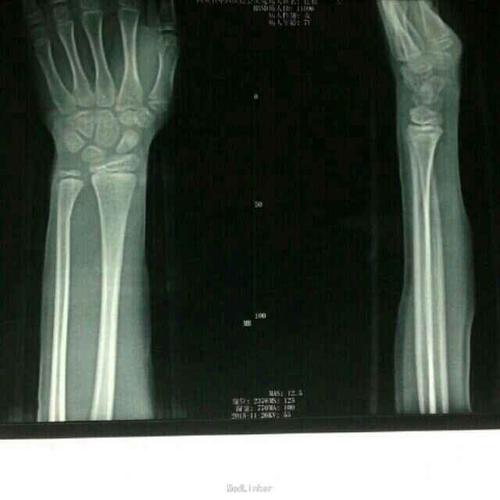

儿童桡骨下段青枝骨折手法治疗

对于小孩尺桡骨青枝骨折,切勿暴力复位,慢工出细活,同样可以达到